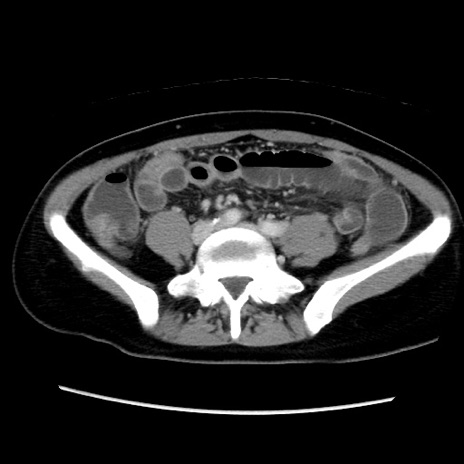

症例39(横断像)

【症例】40歳代女性

【主訴】上下腹部痛

【現病歴】2日目から下腹部痛あり。夜間は痛みで眠れなかった。昨日より上腹部痛と下痢が出現。臥位で痛みは軽快したため、休んでいた。本日になって臥位でも立位でも痛みが強くなってきたため救急要請。

【既往歴】子宮内膜症

【身体所見】部:平坦・軟、左上下腹部に圧痛あり、反跳痛あり。

【データ】WBC 21800、CRP 26.78